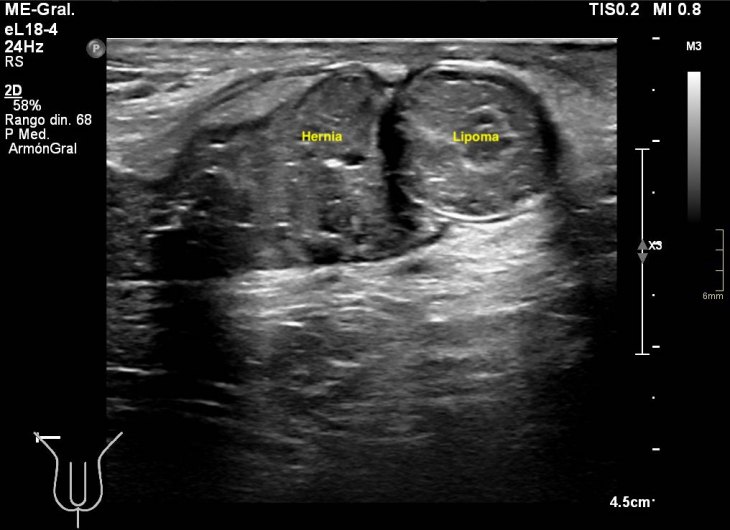

291. Lipoma de cordón y hernia inguinal.

En algunas ocasiones te encuentras cosas muy chulas, sin esperarlas, son esas cosas que no olvidas. Esta semana entró en la sala un paciente para descartar una hernia inguinal, valorada por el cirujano previa a la cirugía. Cuando el paciente se tumbó en la camilla y se descubrió la región inguinal, era evidente que algo pasaba porque tenía un bulto muy llamativo, duro. Justo cuando le puse el traductor y sin tiempo para reaccionar la hernia se corrigió, el bulto desapareció…casi. Me di cuenta que la hernia existía, sin verla, así que me pude a evaluar la región inguinal desde le teste, buscando el canal inguinal…Sorpresa…

Nada más acabar el testículo y empezar el canal inguinal me encontré una estructura hipoecogénica, con septos, con un borde ecogénico a modo de cápsula muy llamativo. La estructura era dura y fija, no respondía a valsalva, enseguida me dí cuenta de que no era parte de una hernia, no era una tripa, porque no se movía…siguiente sorpresa…

Cuando le pedía al paciente que hiciera valsalva, y por el canal inguinal aparecía una hernia muy evidente, con un cuello visible en dos proyecciones, la hernia tenía tanto grasa como asas intestinales, sonaba al entrar y al salir.

Lo más llamativo y lo que más me gustó de la prueba es que cuando la hernia llegaba a la estructura fija que estudié en primera instancia, la abrazaba, se apoyaba en ella y o conseguía moverla…y después retrocedía introduciéndose en la cavidad abdominal.

La hernia era una hernia más, el bultoma me hizo saltar las alarmas y se lo comuniqué al radiólogo responsable. Ante la sospecha razonable de que pudiera ser un tumor, decidió ampliar con un TAC de Pelvis sin CIV que demostró la existencia tumonal benigna que correspondía con un lipoma de cordón, benigno, por su aspecto amable, bordes definidos, tabique externo y centro graso.

Hernia inguinal, con foramen de 15 mm, con introduccion en saco herniario de 3 cms, de grasa omental. Imagen nodular en cordon, distal, de 2 cms, que sugiere patologia benigna.

En una misma región coexistiendo dos figuras patológicas. Fue muy bonito ver que la hernia tocaba el lipoma y retrocedía, disfruté comprobando que los hallazgos ecográficos se confirmaron con el scanner. El caso es precioso y quería que lo vieses, y en esta noche lluviosa y fría, te lo dejo en imágenes…Espero que te guste.

De la imagen 2 a la 5 puedes ver documentado y medido en dos planos con doppler la lesión fija en el cordón.

De la imagem 6 a 8 puedes ver la lesión y su relación con la hernia, en la 6, no se ve la hernia, pero sí el canal inguinal, en la 7 y la 8 observas como la hernia toca el lipoma casi abrazándolo.

La 9 demuestra el contenido de tripas en la hernia.

La 10 y la 11 como la hernia se retira paulatinamente cuando el paciente deja de hacer la maniobra de valsalva.

La imagen 12, lo que corroboraba la sospecha de lesión tumoral en el cordón a expensas de la coexistencia de una hernia en esa localización. Precioso, TODO.